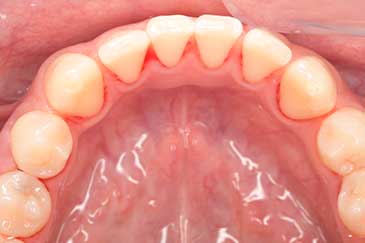

CASE 9

Before

After

基本情報

| 年齢・性別 | 49歳・男性 |

|---|---|

| 主訴 | 定期検診 |

| 治療内容 | スケーリング |

| 治療期間 | 1回30分、2日間 |

| 治療費 | 約1,500円(保険診療) |

| リスク・副作用 | 知覚過敏、出血 |

| 治療方針 | 歯肉縁上歯石を除去してから、14枚法を撮影して歯肉縁下歯石を除去します。歯周ポケットが深く、歯石が残っている部位はフラップ手術を行います。 今後一年程かけて虫歯の治療と並行して歯周病治療、生活習慣の改善を行いプラークコントロールができるように指導します。 |

| 担当者所見 | 久しぶりの歯科医院受診のため、2日に分けて歯石を除去しました。 |